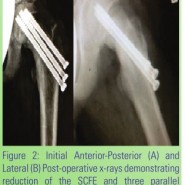

Case Report: We

describe a case where a traumatic unstable SCFE that was initially

treated with closed reduction and fixation with a single transphyseal

screw went on to hardware failure with recurrence of the deformity. The

complication was successfully treated with closed reduction and re-

cannulating the fractured screw within the epiphysis and extracting it

using a conical extraction screw commonly referred to as an “easy out.”

Three trans physeal screws were then placed for improved fixation

strength.  Follow-up at 9 months demonstrates a fused physis and no

signs of avascular necrosis of the femoral head.